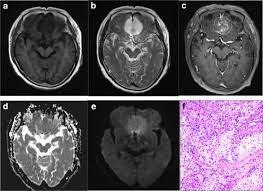

Series 001 — Frontal Lobe Mass (Likely Meningioma) Overview

Initial scan set with key anatomical landmarks and first-pass observations.

Key Finding